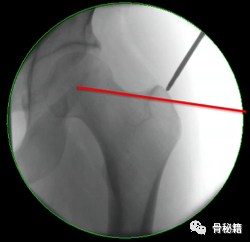

1、进钉点。髓内钉的位置在哪里最合适?

当然是髓腔的最中心,所以髓腔最中心的延长线就是最佳的进钉点。一般位于梨状窝。一个好的进针点可以保证力线,同时进钉后还有复位的作用,如果进钉点出现了偏移,可能整个手术都会有影响。好的开始象征着接下来手术的顺利,一定要取一个好的进针点。

他在正侧位的透视位置我们可以看到位于髓腔中心的延长线上

随着有外翻角的髓内钉的发明,我们现在目前用的可能多是大粗隆顶点进针的了